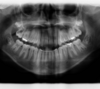

Les radios après le traitement

Vues après le traitement